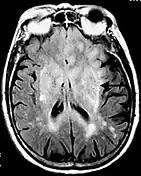

La séquence en inversion-récupération consiste à effectuer une impulsion RF à 180° dans le plan longitudinal avant d'effectuer une séquence écho de spin. Ce type de séquence est notamment utile pour obtenir un meilleur contraste entre les tissus ou bien la suppression du signal de certains tissus comme par exemple le LCR dans la séquence FLAIR (FLuid Attenuated Inversion Recovery)[3] ou de la graisse dans la séquence STIR (Short Time Inversion Recovery)[4].